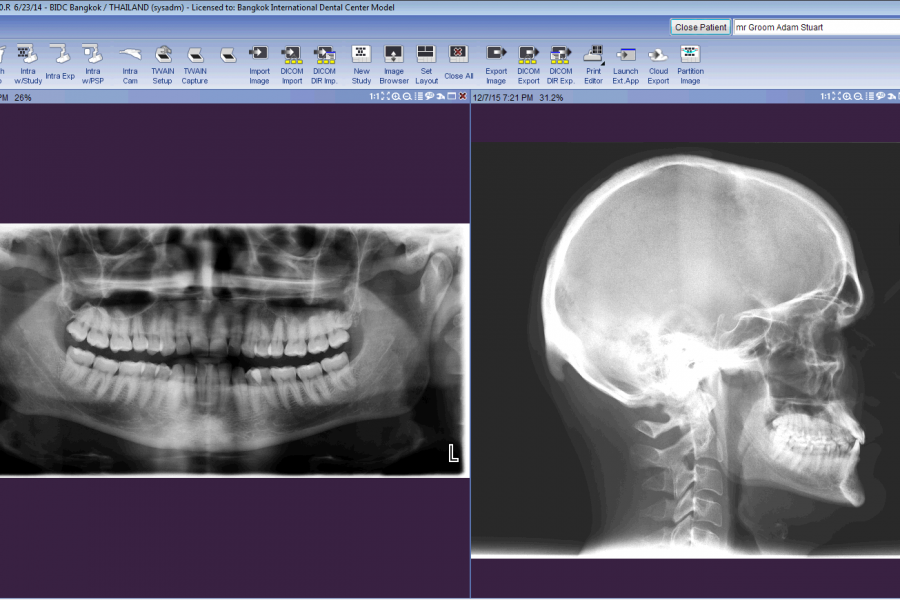

การตรวจวินิจฉัยเป็นขั้นตอนที่สำคัญ อีกขั้นตอนหนึ่งสำหรับทันตกรรมสมัยใหม่ เพื่อการวางแผนการรักษาที่ถูกต้องและ มีประสิทธิภาพมากที่สุด

เทคโนโลยีที่เราเลือกใช้ในการวินิจฉัยโรค

เครื่องมือทางทันตกรรมที่ดีช่วยเพิ่มความสะดวกสบายให้แก่ทันตแพทย์ผู้ใช้ รวมถึงช่วยเพิ่มประสิทธิภาพในการรักษาและเวลาในการรักษาที่รวดเร็วยิ่งขึ้น ดังนั้นเราจึงเลือกสรรแต่ วัสดุ อุปกรณ์และเครื่องมือทันตกรรมต่างๆที่มีเทคโนโลยีที่ทันสมัย และเทคนิคสมัยใหม่ ในการให้บริการ

ศูนย์ทันกรรมของเรามี เครื่องพาโนรามิกเอ๊กซเรย์ (Panoramic x-ray machines) ซึ่งเป็นเครื่องถ่ายเอ็กซ์เรย์ที่ช่วยในการวินิจฉัยโรคและการวางแผนการรักษาที่แม่นยำยิ่งขึ้น ทั้งนี้ศูนย์ทันตกรรมของเรายังสามารถให้บริการด้วยหัองทันตกรรม 10 ห้องเพื่อรองรับจำนวนผู้เข้ารับบริการที่มากขึ้น รวมทั้งทุกห้องยังประกอบด้วย ชุดเก้าอี้ทำฟัน ที่ทันสมัยและได้รับการออกแบบอย่างดีเพื่อให้ความสะดวกสบายสูงสุดแก่ผู้เข้ารับบริการขณะรับการรักษา